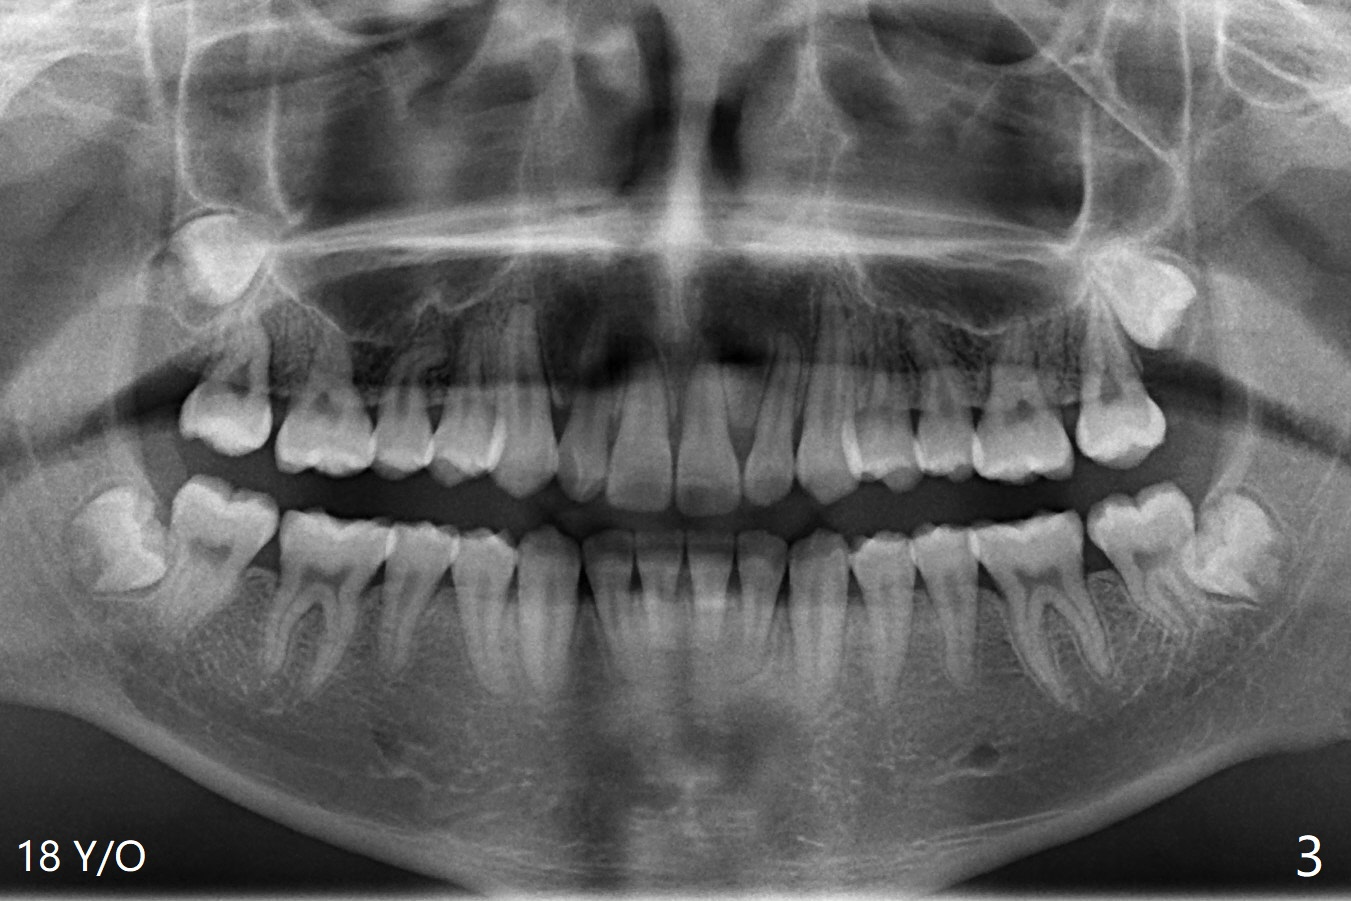

A 22-year-old man will return for 3rd molar extraction (4 of them, Fig.1-4). Prepare 2 or 3 #15 blades and 1-2 extra surgical burs. Since the third molars may overlap with the second ones, oblique incision (red line in Fig.4') will be mesial. Place Collagen and Osteogen plugs in the #32 and 17 sockets, respectively (Fig.4': C, O). As the roots are short and bone formation distal to the 2nd molars is critical, the plugs will be placed horizontally and coronally (Fig.4' white outline). No dovetail is needed. Pan 4 BW will be taken immediately and 3-4 months postop. The experiment will confirm whether collagen plug is enough to facilitate socket bone healing. In fact extraction of #1 turns out to be extremely difficult. There is not enough time for #16 and 17 extraction in one appointment (Fig.5).